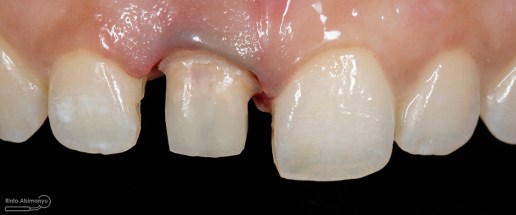

Kondisi setelah crown dibongkar

Kondisi setelah pasak berhasil dikeluarkan